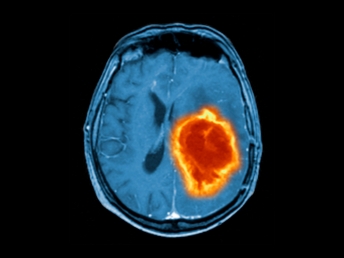

Intracranial Tumors

Certain brain tumors can affect vision by compressing optic nerves or other visual pathways.